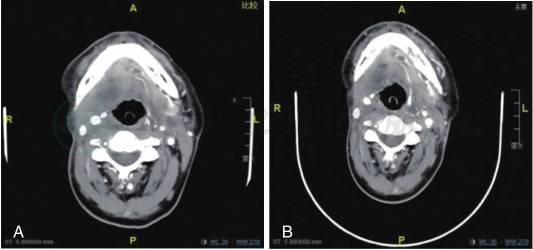

疗效评估:治疗后右颌下肿胀再次缓解,第2周期后评估为部分缓解(PR)(图4A)、第4周期后评估为持续PR;后安罗替尼减量为10mg口服(1年左右减量到8mg),吃14天停7天,维持治疗,疗效评估为:PR(图4B)。

图4

A.右舌颈术后复发靶向治疗中,随访(术区部分组织缺损,可见皮瓣修复,右侧颌下颈部软组织部分缺如,见斑片状致密填充物影。皮瓣后缘及下方、右颌下、颈鞘区、右侧口咽壁见软组织增厚,右咽后、右锁骨上、左侧颈上见肿大淋巴结,中央液化坏死。与2019-04-29老片相比,部分环形强化影消失,范围缩小。)